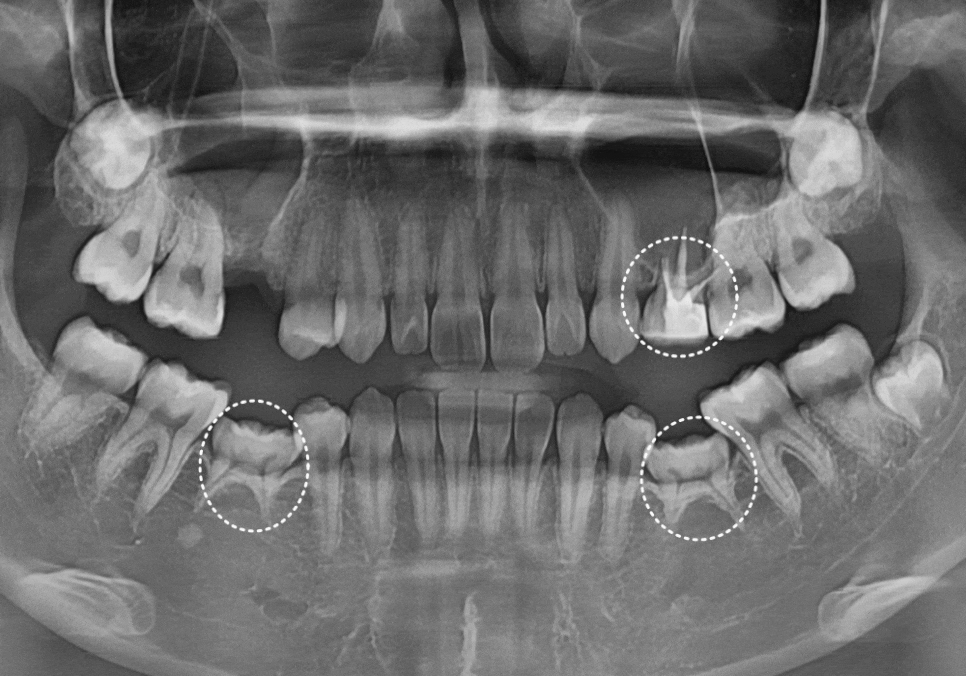

수술 후 약 5개월 동안 임플란트가 뼈와

얼마나 잘 붙었는지 수치로 확인해 보았습니다.

보통 70 이상이면

안전하게 굳었다고 보는데,,

수치가 80 이상으로 매우 높게 측정된 것을 보아,

뼈와 임플란트가 잘 유착된 것을

확인할 수 있었습니다.

임플란트 치아와

신경치료까지만 진행했던 왼쪽 유치도

241018

지르코니아 크라운으로

튼튼하게 보호해 드려

전체적인 치료를 마무리했습니다. ^^

240308(전) 241018 (후)